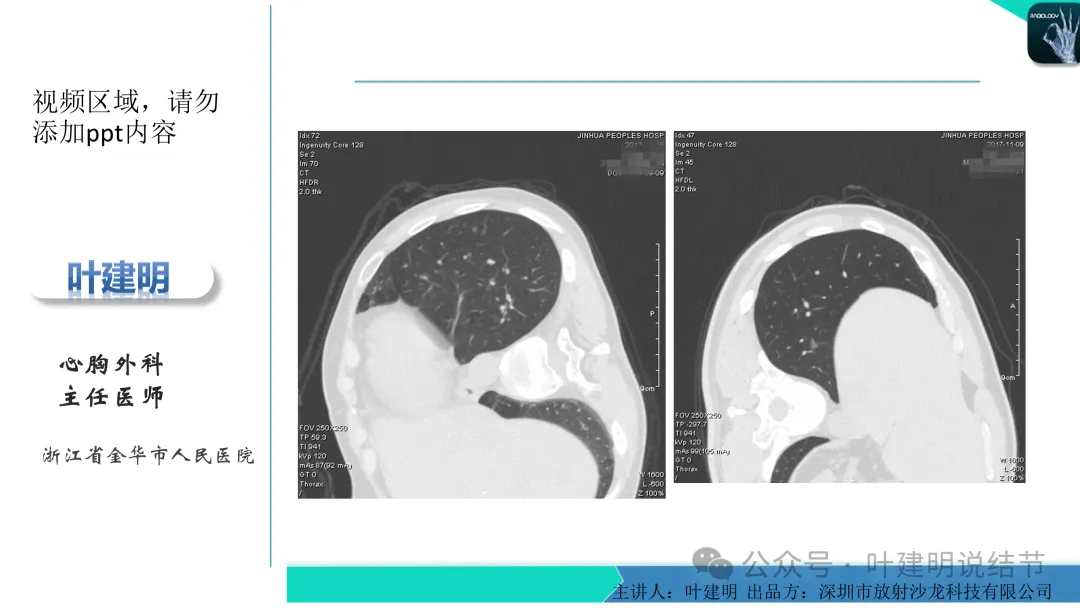

当地说考虑微浸润性腺癌的左下主病灶影像连续层面展示:

病灶出现,显模糊。

上图层面轮廓较清,但密度很淡,似见血管走行,但靠左前方的似条状磨玻璃密度与血管连着的到底是血管分支还是结节的一部分,其实并不确切。如果其实是血管分支,那病灶与它之间就不是空泡。

病灶在此层整体边缘显糊,灶内有空泡似的,瘤肺边界欠清。

边缘不平,还是灶内多发小空泡?邻近血管与之紧贴,但血管无异常走行。病灶密度很低,显糊。

中间所谓空泡更像是细支气管扩张,内壁非常光滑且圆形。

病灶边缘区淡而模糊。

这个病灶会是微浸润性腺癌吗?当然没有病理诊断,我也不能说百分之百必不会,但这样的病灶已经风险大到必得尽快手术切除干预了吗?显然还早着呢:1、影像不是典型的结节状;2、边缘与轮廓模糊不清;3、灶内似有细支气管扩张(更容易是细支气管扩张伴少许周围炎或肺泡上皮增生);4、血管邻近走但无牵拉影响;5、没有实性成分,没有锐利毛刺,没有胸膜牵拉,没有血管进入,没有任何倾向风险性高的影像特点。我一直强调:肺结节是否要干预处理,不要纠结于最后病理是什么,而要看风险高低;而风险高低的最重要术前判断依据一是随访有无进展,二是有没有实性成分。只要没有肉眼可见的影像上的实性成分,风险就是低的!何况病理也是人看的,原位还是微浸润,不典型增生还是原位有时也在一念之间。

早在2020年时,我受邀在《放射沙龙》做过一个系列的精品课,当时专门总结分析过各类良恶性肺结节与肿块的影像特征,这是当时关于微浸润性腺癌影像特征的分析,今天看来仍基本不太需要改变,大家有兴趣的可以参考: